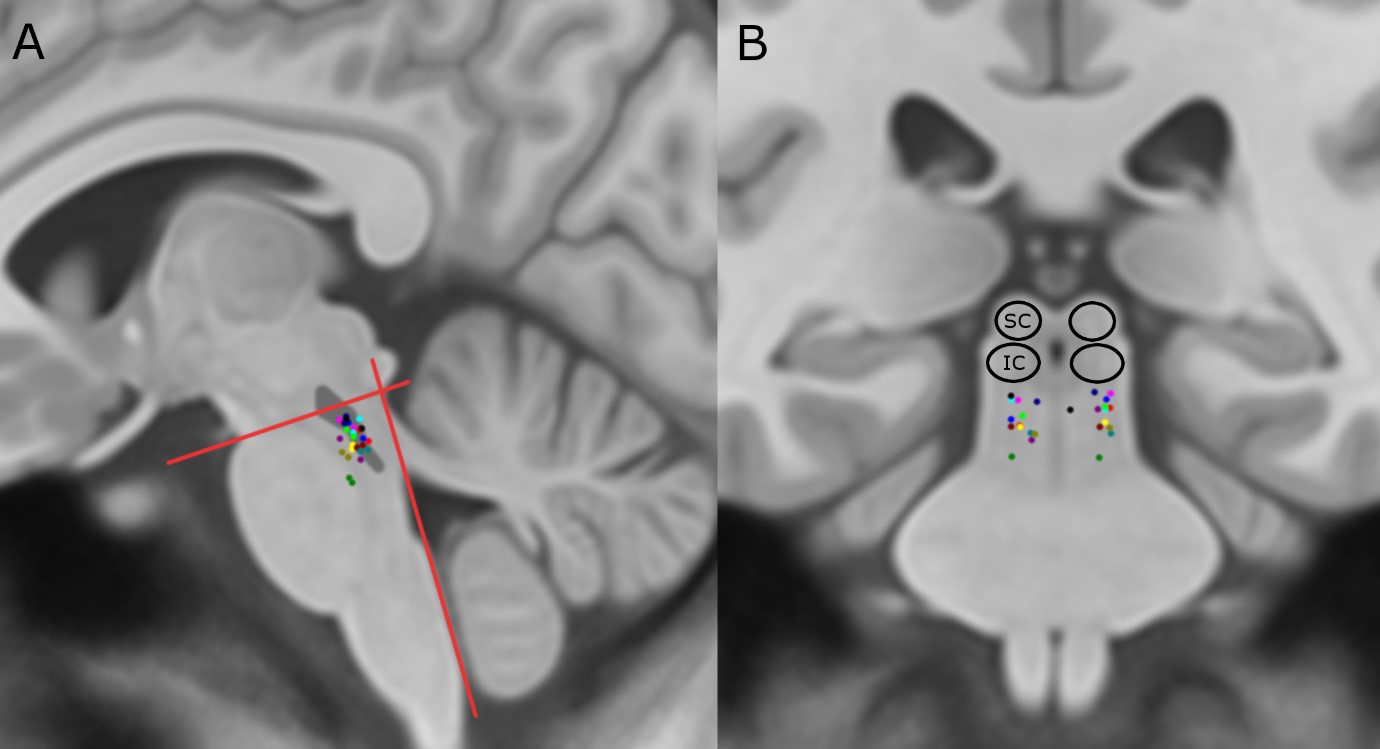

Anticipated locations of sites in the human brain that were targeted for therapeutic electrical stimulation (coloured dots), as looking from the side (A) or the front (B). The relative location of the pedunculopontine nucleus has been outlined in dark grey in the left panel.